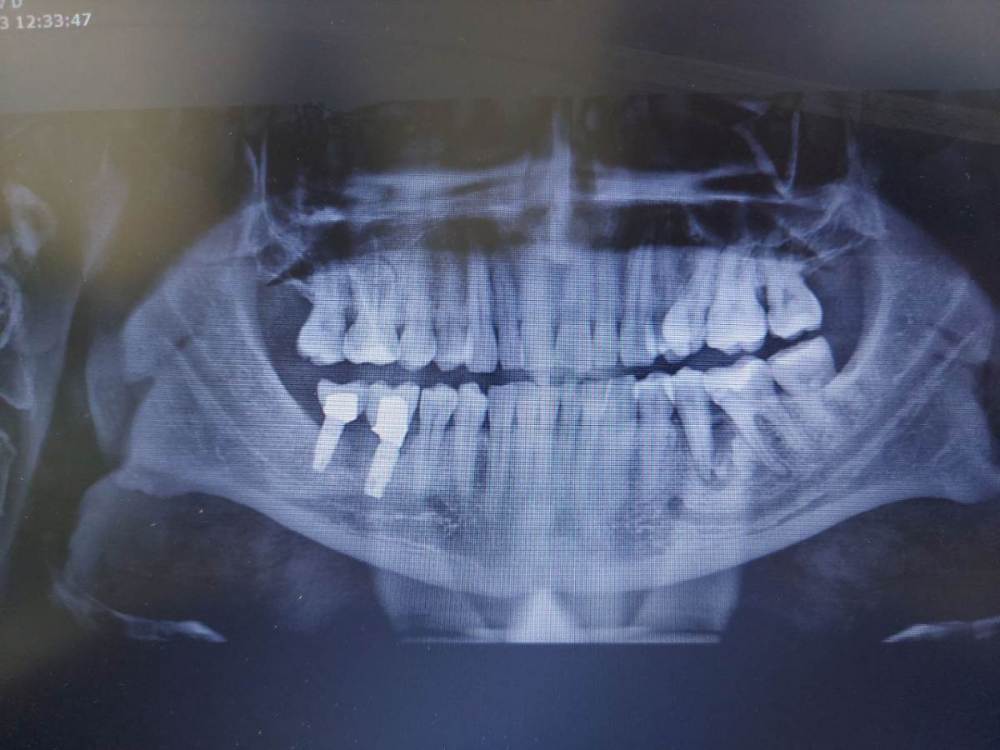

Ольга Я Опубликовано 15 июля, 2023 Поделиться Опубликовано 15 июля, 2023 Добрый вечер. Доктора подскажите пожалуйста!!! Пациент пришёл с жалобами на боли при жевании, в покое ничего не беспокоит. Более 10 лет назад был удалён 36. На его место встали 37,38. Перкуссия "+" 37,38. А вот 35 вообще не беспокоит, у него небольшая стираемость в пришеечной области. Между 35и 37 похоже на остатки корней 36, КТ плохого качества. Какие действия лечения??? Депульпировать 35,37 и ревизия хирургическая???Удалить 35 и хирургическая ревизия??? Другие варианты??? Ссылка на комментарий

Ольга Я Опубликовано 15 июля, 2023 Автор Поделиться Опубликовано 15 июля, 2023 Большое разряжение в области 35. Хирурги рекомендуют депульпировать 35 перед хирургической ревизией, а я сомневаюсь. Он витальный и перкуссия "-". Вот и хочу послушать мнения докторов!!! Ссылка на комментарий

АнтонТЛТ Опубликовано 15 июля, 2023 Поделиться Опубликовано 15 июля, 2023 Делать ревизию, а потом проверять витальность 35. Можно сделать шаблон для бокового доступа к корню 36, чтобы 35 не повредить. 1 2 Ссылка на комментарий

Carioznik Опубликовано 16 июля, 2023 Поделиться Опубликовано 16 июля, 2023 (изменено) 6 часов назад, Ольга Я сказал: Хирурги рекомендуют депульпировать 35 перед хирургической ревизией Зачем перед? Что это даст - ничего (просто "убъете" зуб, так сказать, на всякий случай). Сначала хирургия , а потом проверка на витальность через 2 недели. Изменено 16 июля, 2023 пользователем Carioznik 1 1 Ссылка на комментарий